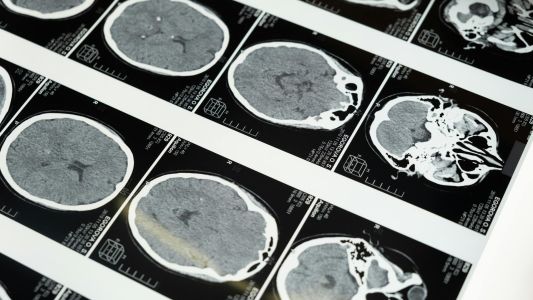

Multislajsni CT skener glave omogućava detaljne preseke mozga i tkiva glave. Koristi se pri sumnji na povrede, krvarenja, tumore i neurološke poremećaje. Pregled je bezbolan, kratak i bezbedan.